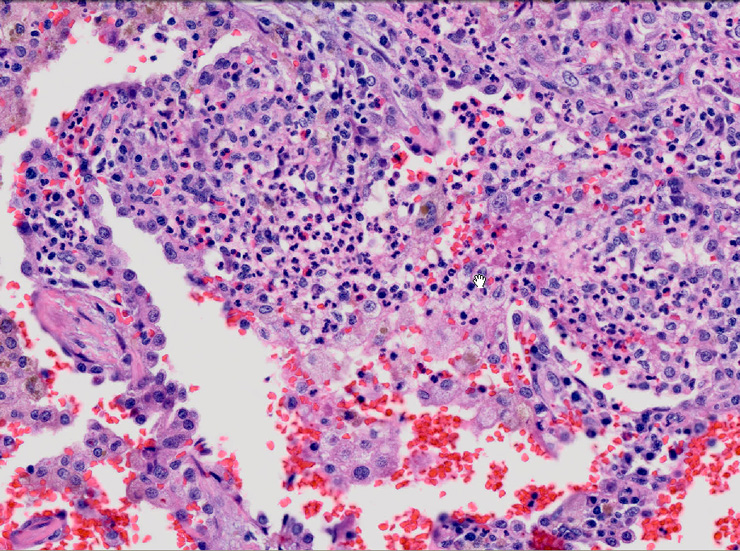

肺毛細血管炎 capillaritis

肺胞壁に多数の好中球浸潤。肺胞腔内に出血。 capillaritisが起こるWegener' granulomatosis劇症型には, なかなか肉芽腫性病変を見つけることは難しい

capillaritisの組織所見*17

Fig.01 capillaritisと肺胞出血Fig.02 Fig.01拡大像